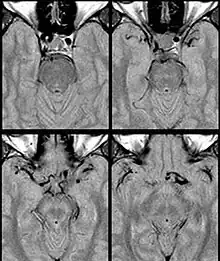

Internal carotid artery dolichoectasia is particularly interesting because the artery normally already contains one hairpin turn. Seen in an MRI as two individual arteries at this hairpin, a carotid artery dolichoectasia can progress so far as to produce a second hairpin turn and appear as three individual arteries on an MRI. In the case of a dolichoectasia of the Internal Carotid Artery (ICD), the pathogenesis is primarily related to compression of the optic nerves at the optic chiasma (see Fig. 1 and 2).